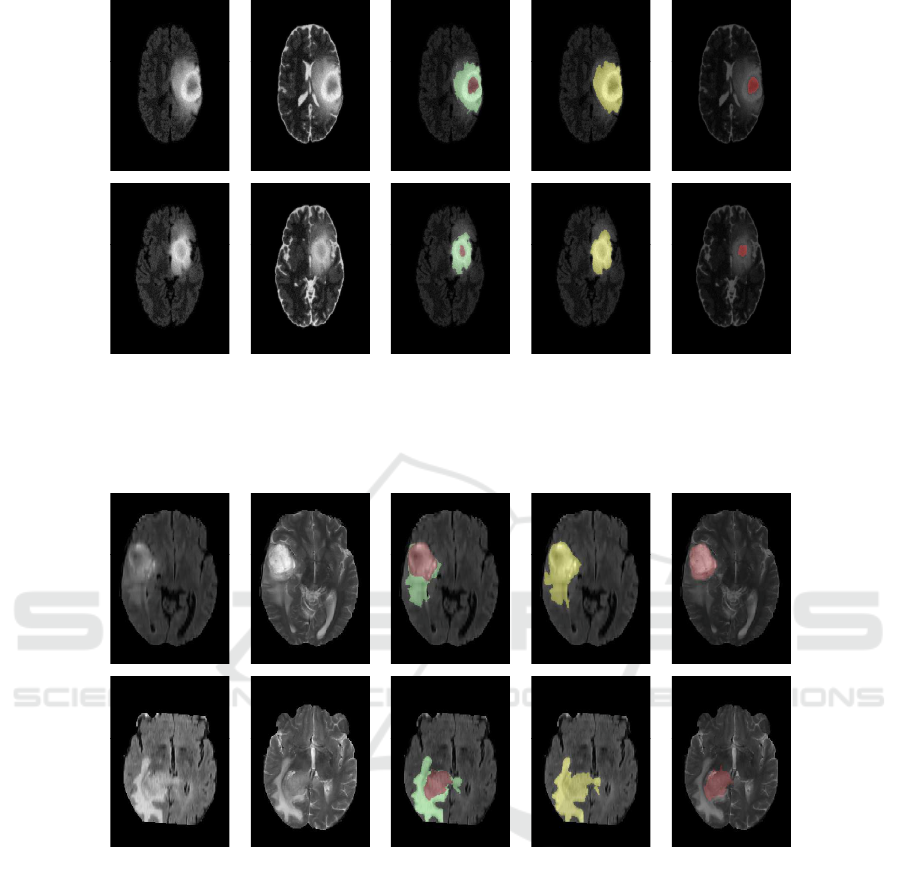

(a) FLAIR slice (b) T2 slice (c) Ground

Truth

(d) Whole

Tumor Segmen-

tation

(e) Necro-

tic Tumor

Segmentation

Figure 4: Segmentation results of Synthetic High Grade Gl ioma Tumor (1st row ) and Synthetic Low Grade Glioma Tumor(2nd

row).

Segmentation resu lts with the proposed alg orithm

are shown in fig. 5, fig. 3, and fig. 4 for High Grade

Real, Low Grade Real and synthetic tumors respecti-

vely. Each row represents (from left to rig ht) FLAIR

slice, T2 slice, Gr ound Truth, Whole tumor segmenta-

tion in FLAI R slice, Necrotic tumor segmentation in